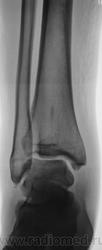

Первое, что приходит на ум, - это обызвествление сухожилия. А вот очажок в проекции дистальной части б\б кости, что это?

А вот очажок в проекции дистальной части б\б кости, что это?

может это insula compacta?

Или эностоз, что одно и тоже.